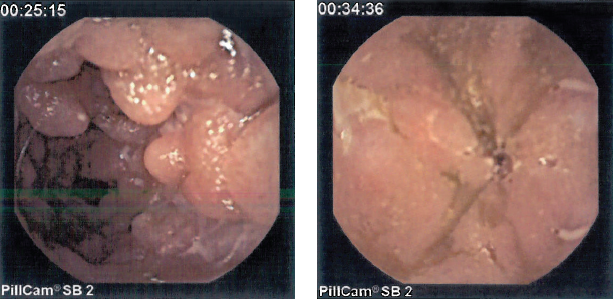

The boy underwent capsule endoscopy, in which a pill-camera was inserted into the digestive tract and photographed the proximal small intestine beyond the reach of the endoscope.

There, in the patient’s jejunum, photographic evidence of Crohn disease was visualized—specifically, pseudopolyps (Figure 2) and ulcers (Figure 3).

Figure 2. Capsule endoscopy images revealed pseudopolypoid manifestations of inflammatory bowel disease in the jejunum.

Figure 3. Photographs of the wall of the small intestine showed jejunal ulcers, leading to a diagnosis of Crohn disease.